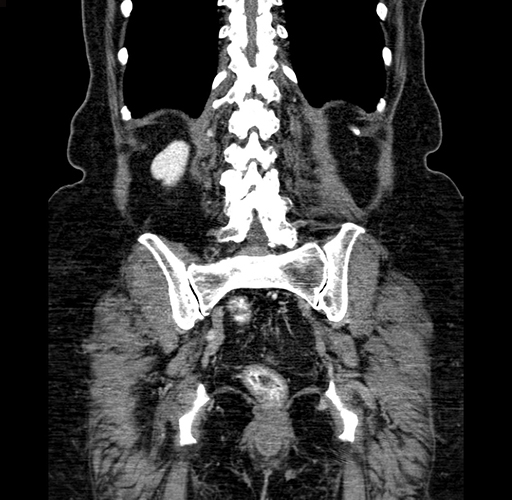

Pre-Chemo: Coronal Venous

Coronal Venous